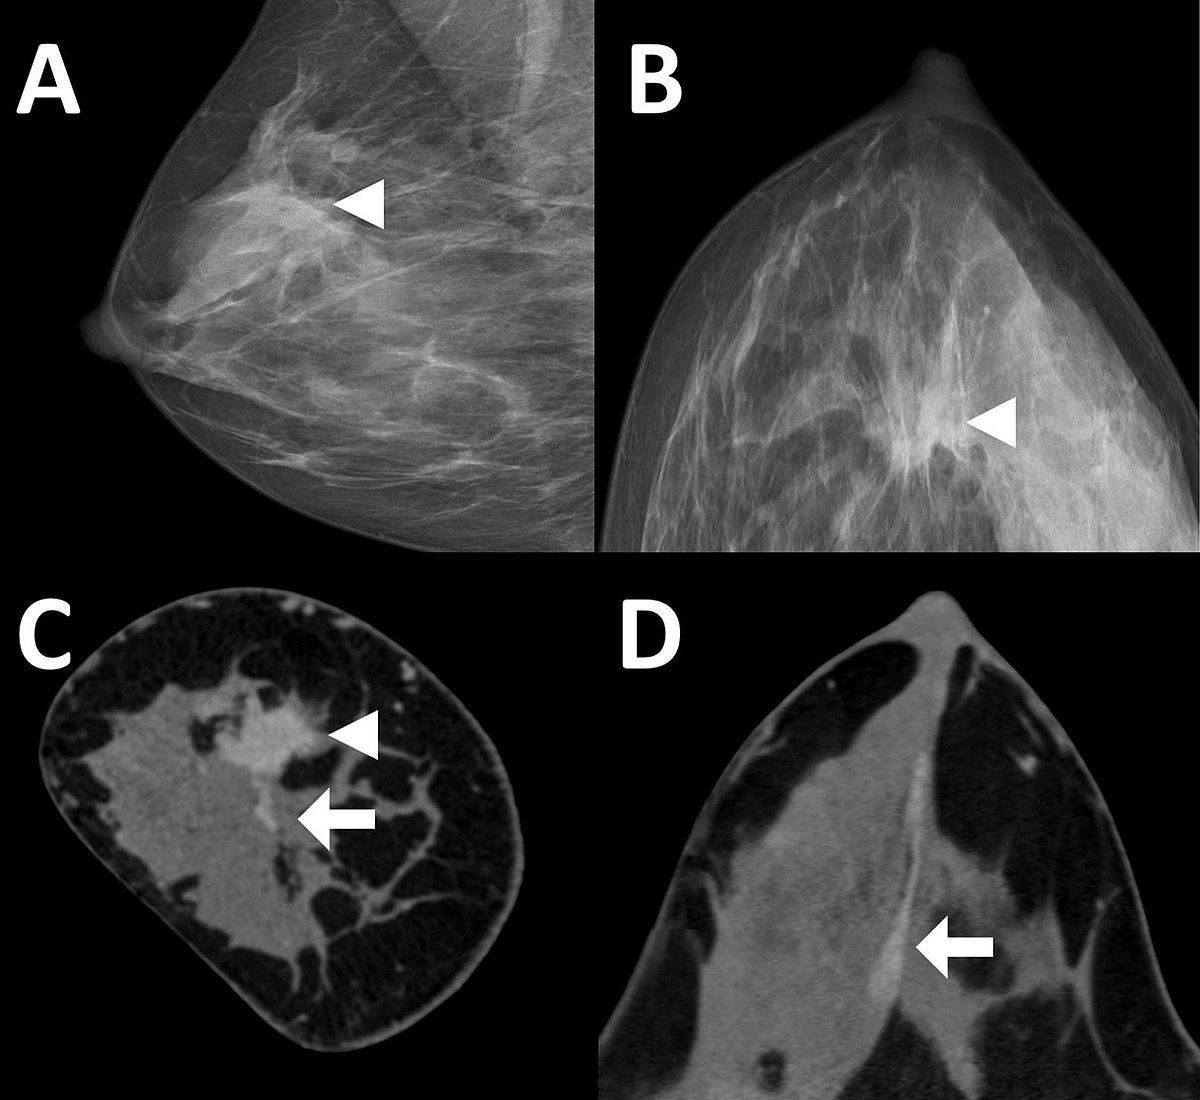

- Spiral-Brust-CT mit Photon-Counting CT:

Eine neue Methode zur Brustuntersuchung – die Spiral-Brust-CT (SBCT) mit PCCT-Detektor – ermöglicht eine besonders detailreiche 3D-Bildgebung ohne schmerzhafte Brustkompression. Sie zeigt vielversprechende Ergebnisse in der Diagnose von unklaren Befunden und zur Operationsplanung. (Wetzl et al.)

- Wetzl M, et al. Spiral breast computed tomography with a photon-counting detector (SBCT): The future of breast imaging? Eur J Radiol. 2022 Dec;157:110605. doi: 10.1016/j.ejrad.2022.110605

- Wetzl M, et al. Detection of Microcalcifications in Spiral Breast Computed Tomography with Photon-Counting Detector Is Feasible: A Specimen Study. Diagnostics (Basel). 2021 May 9;11(5):848. doi: 10.3390/diagnostics11050848